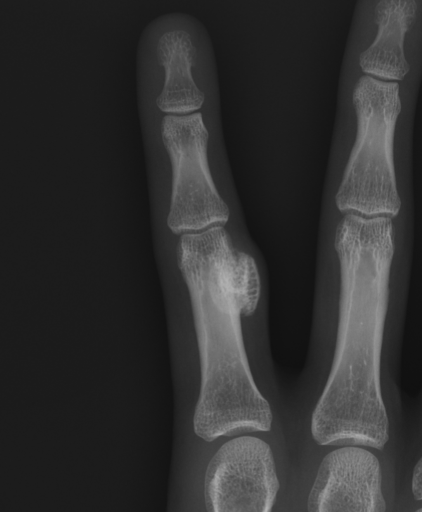

X-ray

Well defined bony mass arising from the surface of the bone

- no medulla

Lesion not continuous with adjacent with cortex